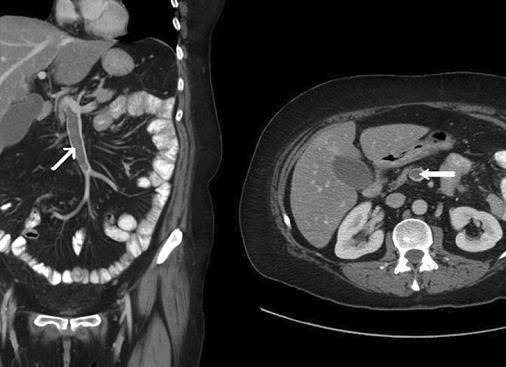

УЗИ брюшной полости является не слишком сложной, но достаточно эффективной процедурой, которая дает уникальную возможность врачам оценить состояние внутренних органов, а также установить их размеры и другие важные критерии для лечения. Подробнее ...